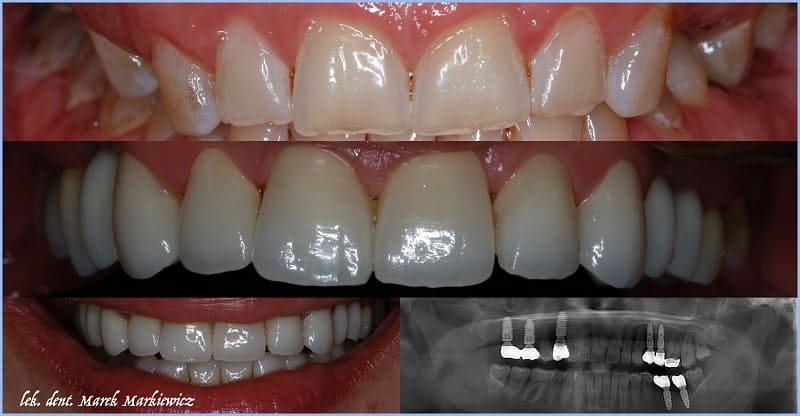

Each dentist in this facility has innovative diagnostic equipment, including a modern, only digital X-ray laboratory, including CBCT 3D tomograph and its own digital prosthetic laboratory, equipped with in laboratory scanners and milling machines, which allows for the production of veneers, crowns and implants even during one visit.